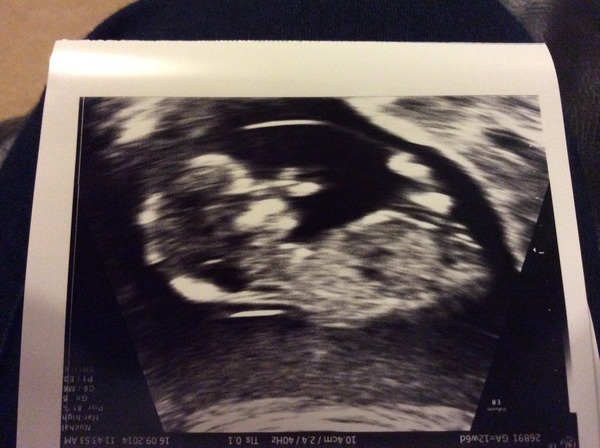

On a (selfishly) more positive note, scan pic from today below... Took ages to get a good one. A very misbehaving wriggler.

Ahh kettle lovely picture

Oh and great pic kettle :)

Lovely scan pictures everyone!

Lovely scan pics. Just under 4 weeks til my 20 week scan, can't wait.

Lovely scan pictures everyone! Mine is totally blurry, even the 4d one. (My doc switched to 4d - is it actually called that btw? Or 3d? But you know what I mean! - and that was amazing! Never had one before!)